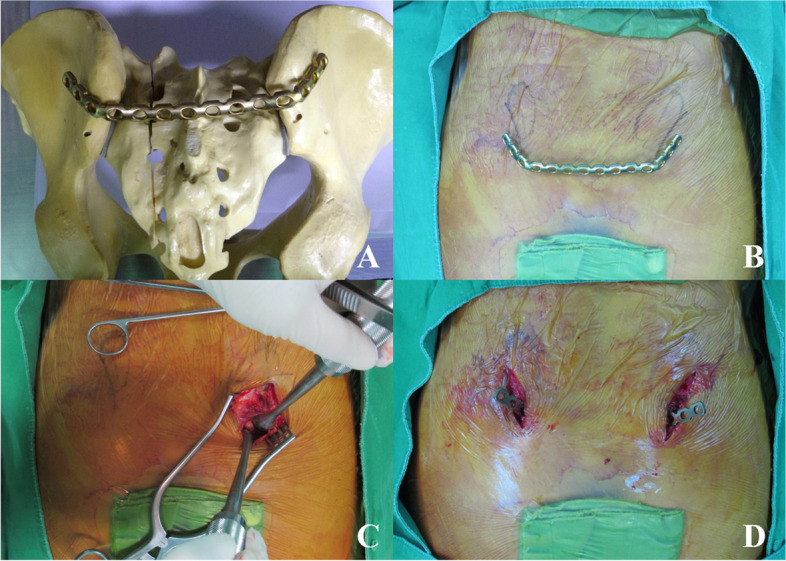

Percutaneous posterior transiliac plate fixation

With the patient in the prone position, 3-cm dual vertical incisions were made lateral to the posterior superior iliac spine (PSIS). After the PSIS was exposed, the superficial fascia was incised along the direction of its fibers and retracted. The gluteal muscles were stripped away from the outer plate of the ilium, and pre-bent 3.5-mm reconstruction plates were inserted just below the posterosuperior iliac spine to one side following resection of the S3 spinous process under fluoroscopy. The plate was inserted into the opposite side through the subcutaneous tunnel and placed on the dorsal side of both ilia. We used at least 3 screws for side, minimum 6 screws were inserted entirely. Finally, the screws were positioned to penetrate the bony cortex on both sides. The details of process for surgical technique of transiliac plate fixation is shown in Fig. 1 [14–16].

Fig. 1.

The percutaneous plate fixation technique. A Preparation of pre-bending in plate reconstruction is conducted using a plastic pelvis bone. B The incision is drawn at the lateral side of the posterior superior iliac spine. C The posterior superior iliac spine is exposed following the dissection of the superficial fascia. D The plate is inserted through the subcutaneous tunnel, and the plate is located on the dorsal side of both ilia